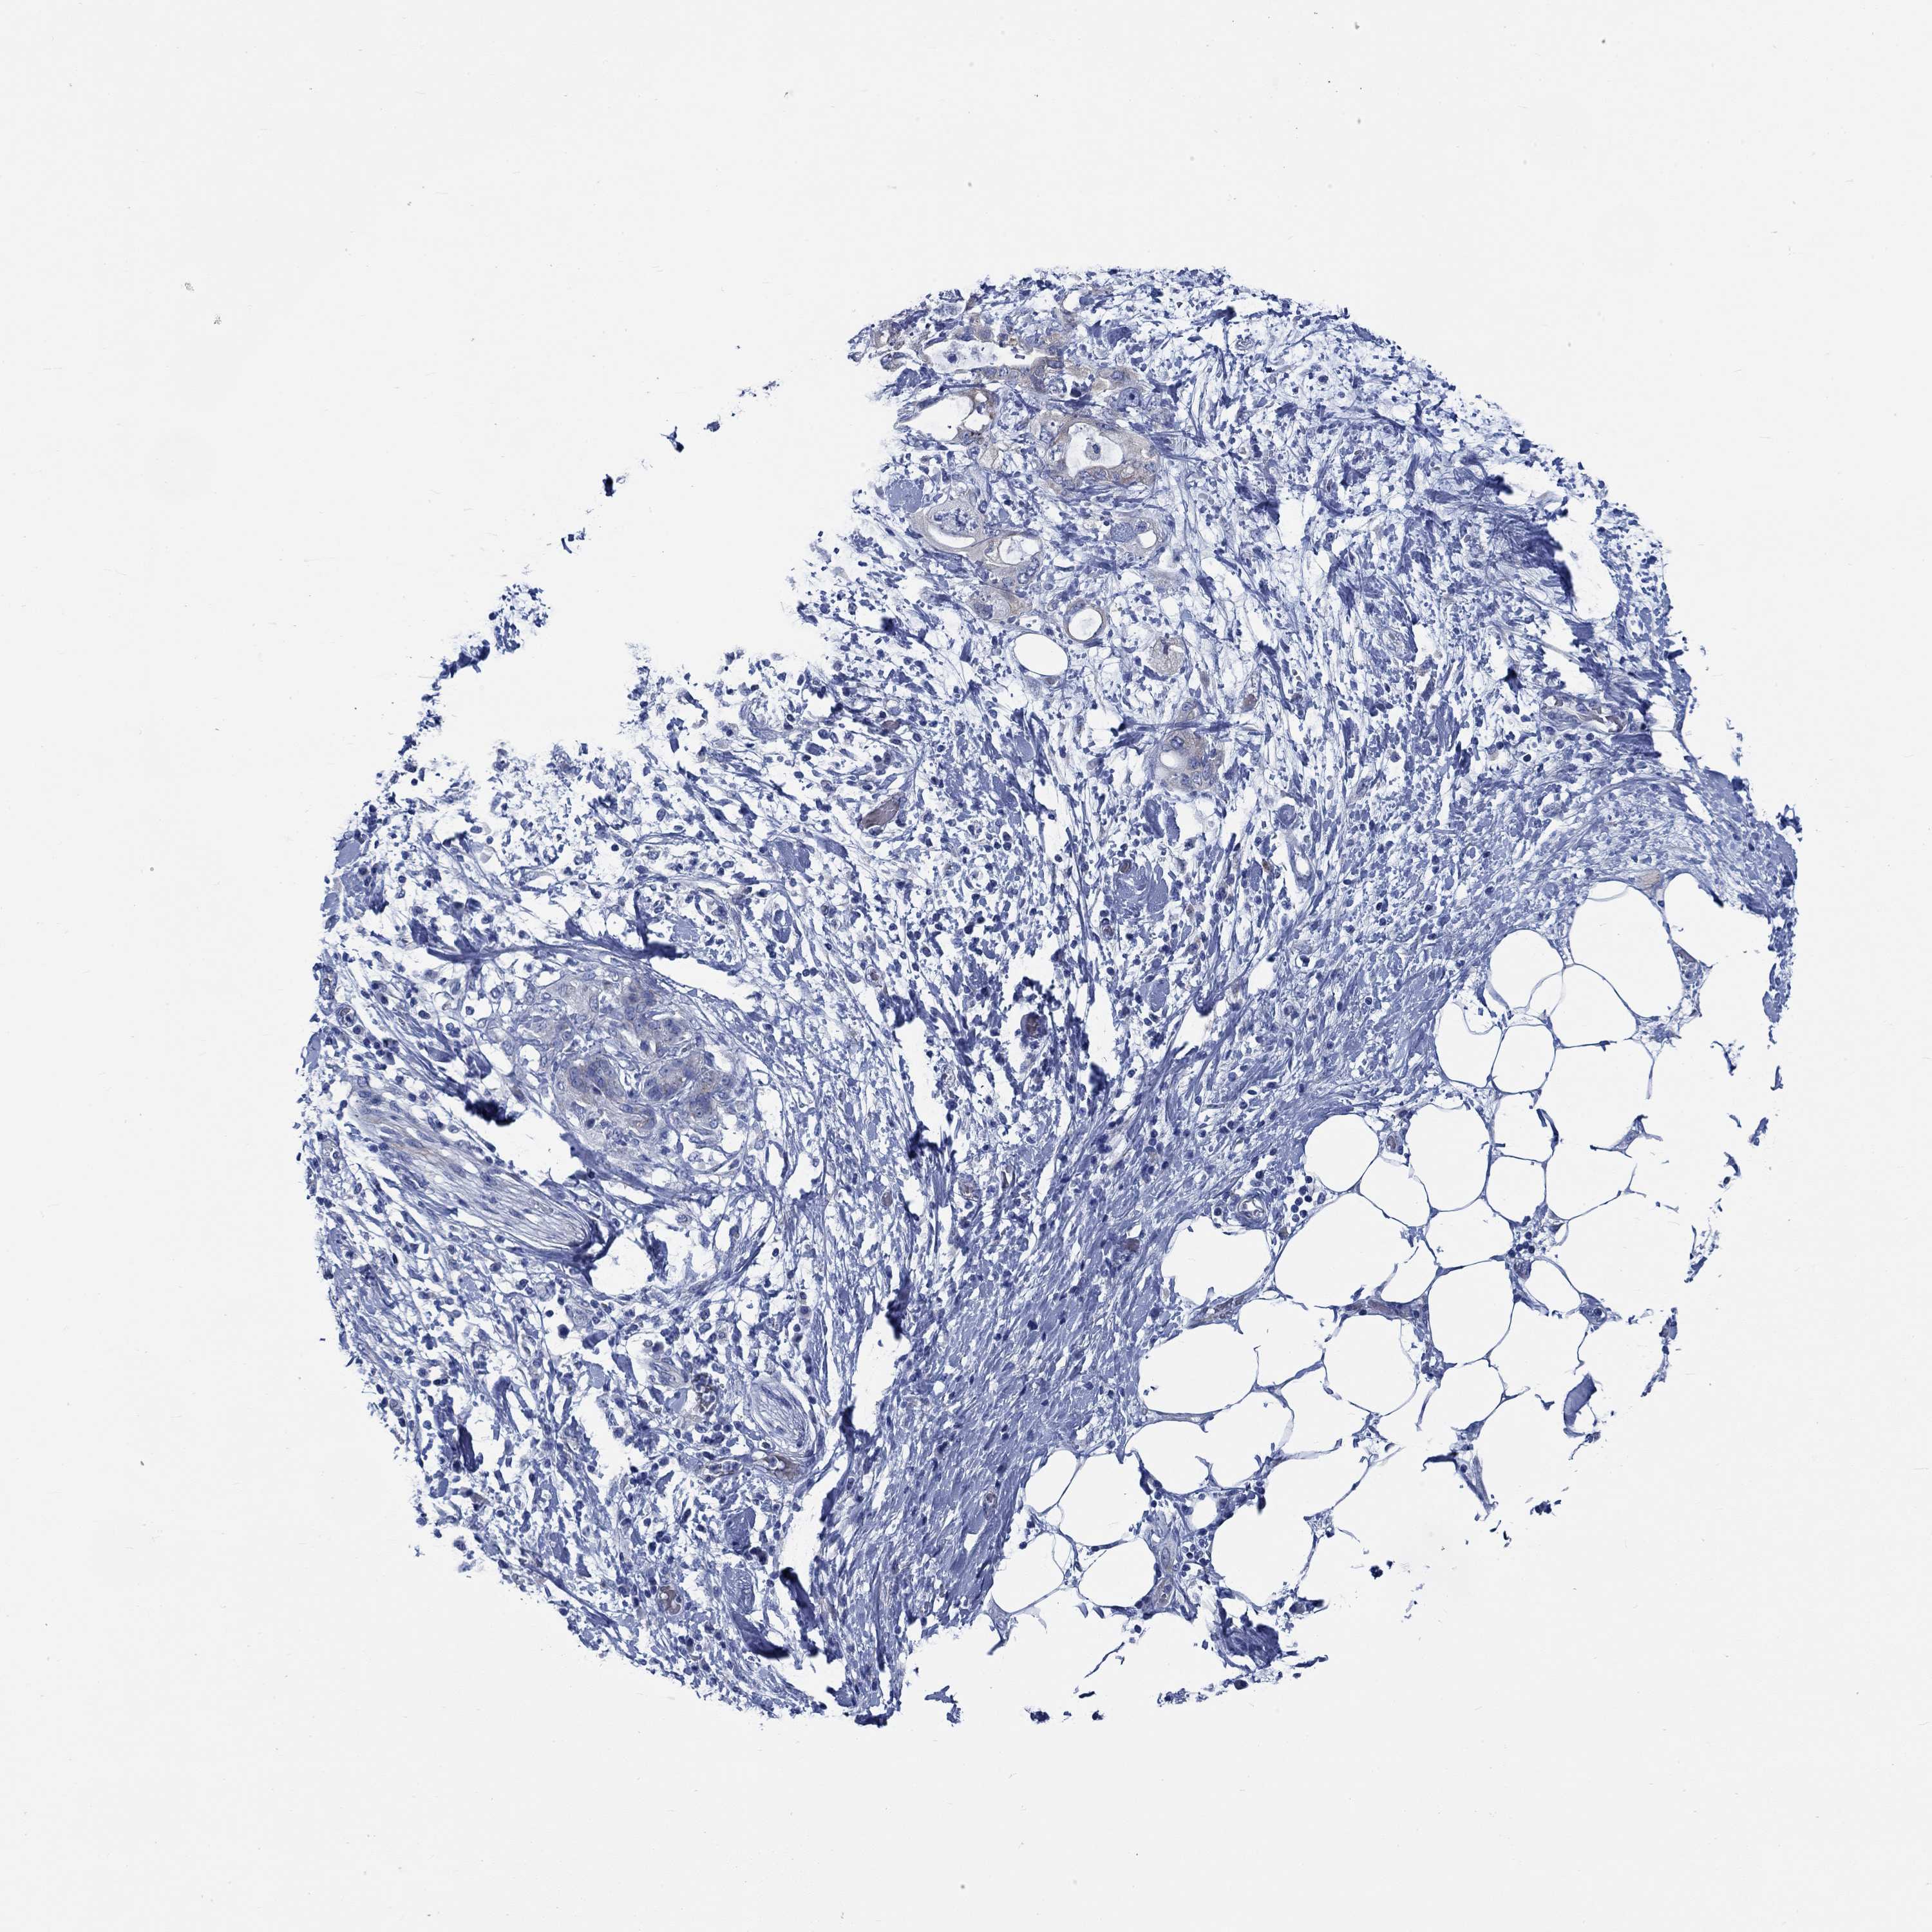

PANCREATIC CANCER - Protein expressioni

A mouse-over function shows sample information and annotation data. Click on an image to view it in a full screen mode. Samples can be filtered based on level of antibody staining by selecting one or several of the following categories: high, medium, low and not detected. The assay and annotation is described here.

Note that samples used for immunohistochemistry by the Human Protein Atlas do not correspond to samples in the TCGA dataset.

Antibody stainingi

Antibody staining in the annotated cell types in the current human tissue is reported as not detected, low, medium, or high, based on conventional immunohistochemistry profiling in selected tissues. This score is based on the combination of the staining intensity and fraction of stained cells.

Each image is clickable and will lead to virtual microscopy that enables deeper exploration of all samples and also displays staining intensity scores, fraction scores and subcellular localization as well as patient and tissue information for each sample.

Antibody HPA020610

Antibody HPA021520

Adenocarcinoma, NOS